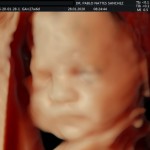

Los objetivos más importantes de esta ecografía son la evaluación de:

- La vitalidad y el bienestar fetal (Doppler).

- Crecimiento fetal.

- Las estructuras anatómicas fetales: diagnóstico de Malformaciones Estructurales de aparición tardía (displasias esqueléticas, alteraciones cardiacas pequeñas, alteraciones la vía urinaria y obstrucciones intestinales.

- Rastreo de alteraciones cromosómicas (sensibilidad del 55% aprox.).

- El escenario Gravídico: Placenta, liquido y Anexos.

- El Doppler de las arterias uterinas maternas y determinación de riesgo para pre eclampsia severa.